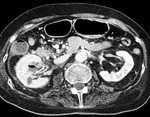

[画像診断]側頭骨骨折について 2010-08-16